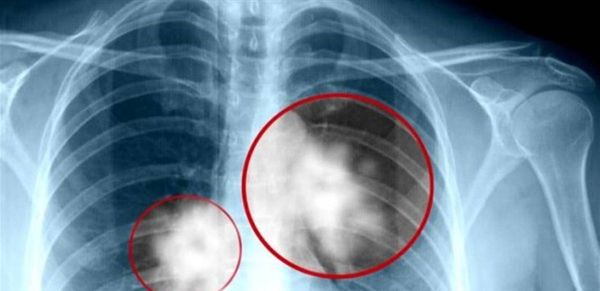

هذا الحاجز يمنع البروتين الطافر من الوصول إلى "مركز إعادة التدوير" داخل الخلية حيث يتم عادة تكسيره، فيبقى البروتين نشطًا ويدفع نمو السرطان. وقد أكد الفريق هذه النتائج عبر فحص عينات أنسجة مأخوذة من 29 مريضًا بسرطان الرئة، حيث وُجدت مستويات مرتفعة من P2Y2 وintegrin β1 في الأورام مقارنة بالأنسجة السليمة المجاورة.